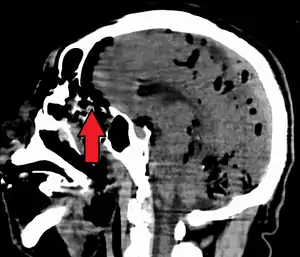

Pneumocephalus is the presence of air or gas within the cranial cavity. It is usually associated with disruption of the skull: after head and facial trauma, tumors of the skull base, after neurosurgery or otorhinolaryngology, and rarely, spontaneously. Pneumocephalus can occur in scuba diving, but is very rare in this context.

| Pneumocephalus and comminuted fracture of the frontal sinus |